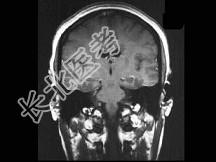

- 单项选择题男,32岁, 头痛、抽搐3年余,MRI检查如图, 最可能的诊断是 ( )

A、先天发育不全

B、灰质异位

C、正常颅脑

D、片状脑梗死

E、脑水肿